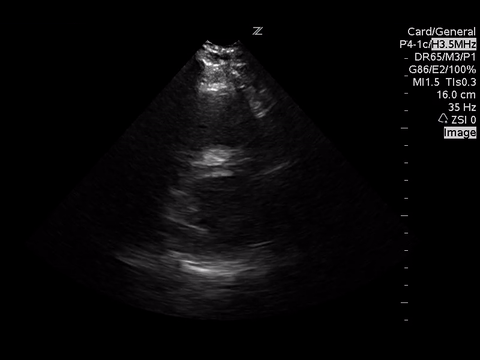

Below are three cardiac views. Think of what you would be looking for given the clinical scenario.

| PSSA |

Mostly with intermediate point of care echocardiography, in this patient, we would be looking for gross LV function using the “eyeball” method, presence of a pericardial effusion and rough RV:LV size.

In these images, we can estimate that the LV function is grossly normal and there is no pericardial effusion. Unfortunately, due to quality, we are unable to comment on the RV:LV size ratio. However, we would be looking for a RV:LV ratio of 0.6:1 as normal with a ratio of 1:1 as severe RV dilation.